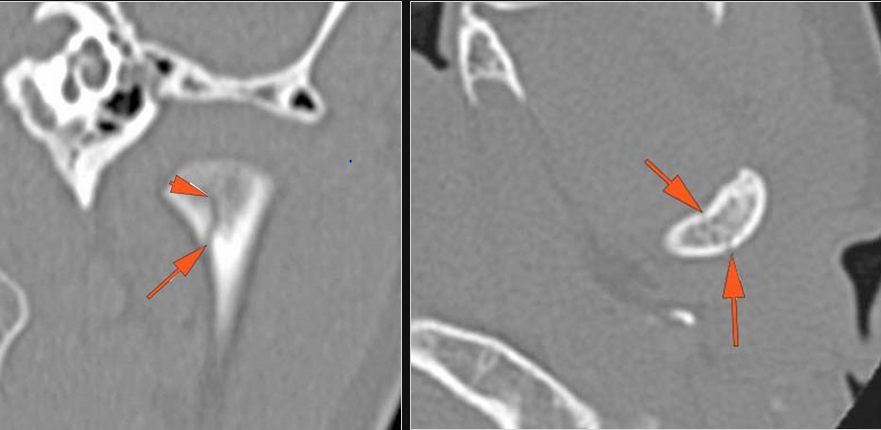

The mesial naso-orbito-ethmoid complex is fractured. Specifically, there is bony injury of the nasal bones or the frontal process of the maxilla and the medial walls of the orbit are abnormal. |

Yes | NA |

The nasolacrimal canal is fractured. |

There is injury of the ethmoid complex. Specifically, the ethmoid roof, olfactory fossa and the cribriform plate are fractured and/or significantly dehiscent. |

The the zygomatic arch, frontozygomatic suture or infraorbital rim are fractured. |

The lateral wall of the orbit is fractured. |

LeFort type III, orbital zygomatic and orbital floor and fronto - naso-ethmoidal complex fractures with possible injury optic nerve/sheath - extent described above.